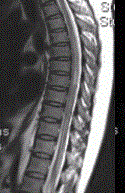

- 多项选择题3.关于MRI的描述正确的是(提示患者行脊柱MRI平扫及增强检查,显示如下图)

A、颈髓增粗,其内可见片状高信号影

B、胸髓可见多发片状高信号影

C、脊髓未见异常

D、MRI增强检查可见片状强化

E、脊髓空洞

F、脊髓肿胀